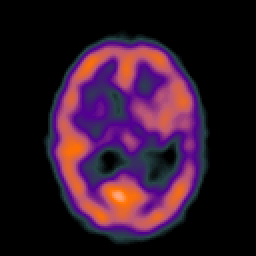

Metastatic bronchogenic carcinoma, overlay -- Slice #12

[Home][Help][Clinical] Slice 12